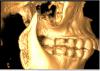

Большой Зеленый Опубликовано 13 марта, 2013 Поделиться Опубликовано 13 марта, 2013 Чтобы получить полезную информацию нужны снимки .Ортопантомограмма,Телерентгенограмма,фотографии моделей челюстей ,фото во рту ... Ссылка на комментарий

Юлианко Опубликовано 13 марта, 2013 Автор Поделиться Опубликовано 13 марта, 2013 Чтобы получить полезную информацию нужны снимки .Ортопантомограмма,Телерентгенограмма,фотографии моделей челюстей ,фото во рту ...Надеюсь это подойдет Ссылка на комментарий